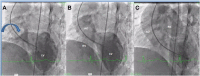

Figures 7

Right ventricle (RV) angiography on anteroposterior view showed (A) filling of left ventricle (LV) through ventricular septal defect and blind pulmonary end (marked by vertical arrow) towards LV; (B) aorta arising from RV and (C) filling of pulmonary artery from aorta through aortopulmonary window (marked by curved arrow).